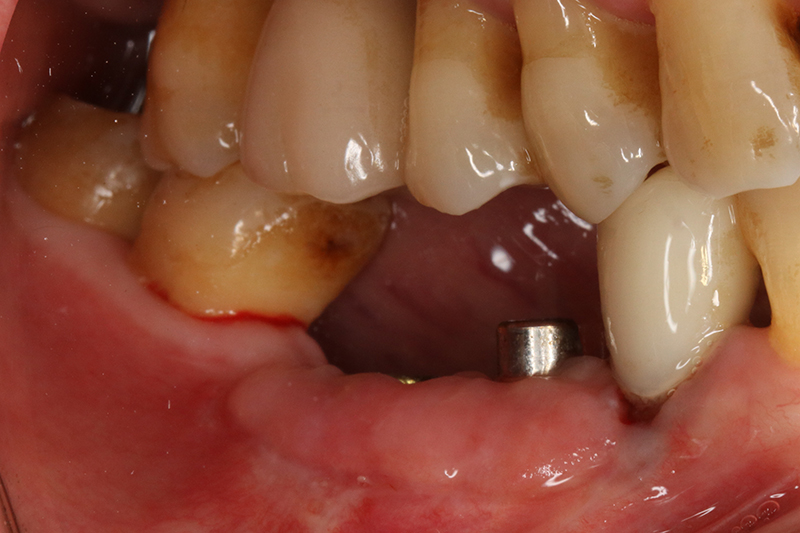

缺牙多顆

案例一

術前

術中